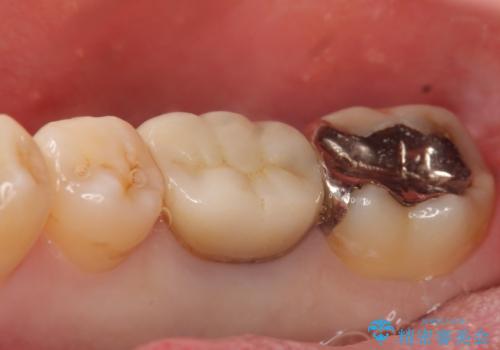

- 数年前から歯茎から膿が出る、治療してもよくならないので診て欲しいといらっしゃった方の症例です。

再根管治療を行い膿の出口の消失及び根尖病変の縮小を確認後、オールセラミッククラウンによる補綴を行いました。